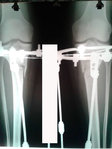

Здравствуйте Николай Николаевич, Наталья! Как у Вас дела? У меня все хорошо, чувствую себя отлично. Хожу свободно. Вот высылаю рентген снимки 90 дней. Но, мне кажется плохо видно? Жду от Вас ответа, надеюсь, ой даже очень, что сращение хорошее! Спасибо заранее!

Здравствуйте, А.! Костная мозоль не плохая, но учитывая слабое состояние костной ткани (слабые кости) во время операции, ещё месяц ходим в аппаратах. Через месяц можете приезжать на снятие аппаратов, рентген сделаете на месте в клинике. С собой привозите костыли.